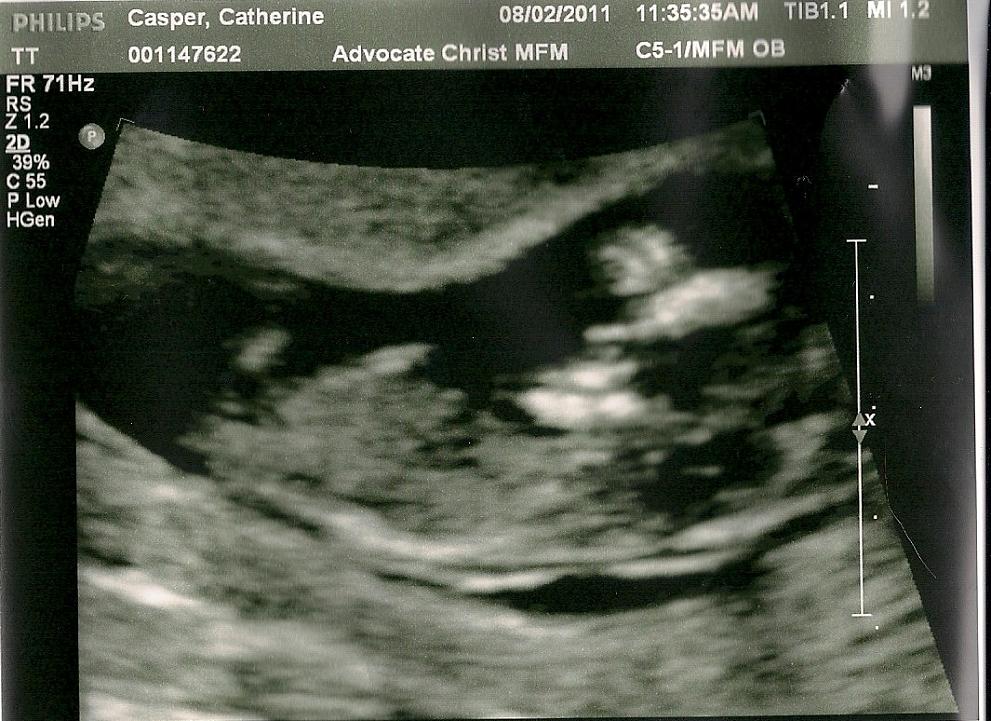

Contest to name the baby, sure. No pictures of the baby bump. But I will share the ultrasounds.

MrsSledn 02:50 PM 08-02-2011

12 1/2 weeks along... Baby is well. Started genetic testing today. Which included a long ultrasound and a finger prick blood test.

The baby's heartbeat was strong and steady at 164 beats per minute. Baby was moving around a lot and being difficult to get the pictures the tech needed. However, the baby did have a hiccuping fit and then waved at me!

:-) At one point baby decided to flip over and looked like they were going to start swimming. It was really good to see the baby and exciting.